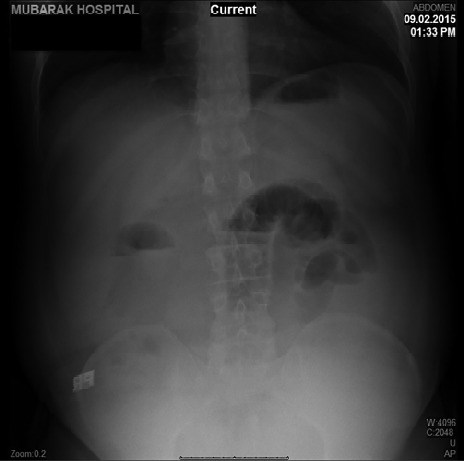

Acute appendicitis is the most common surgical condition with which patients present in emergency departments worldwide. It is also a rare cause of intestinal obstruction. Here, we report a case of a 53-year-old man who presented with a clinical picture of mechanical small bowel obstruction. Leucocytosis was not demonstrated on the routine blood investigation in our case, in contrast to the findings for most patients with acute appendicitis. Acute appendicitis, as the cause of the intestinal obstruction, was diagnosed by computed tomography of the abdomen. The patient was treated using diagnostic laparoscopy and laparoscopic appendectomy. This case was compared with those previously reported in the medical literature to determine the frequency of the case and the surgical management.